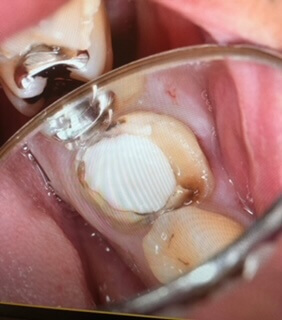

右上8番(右上の親知らず)をドナーとして用いました。移植後は安静を保たなければならないため前もって噛み合う面を削っています。

縫合糸と強い接着剤を用いて移植歯を固定しています。